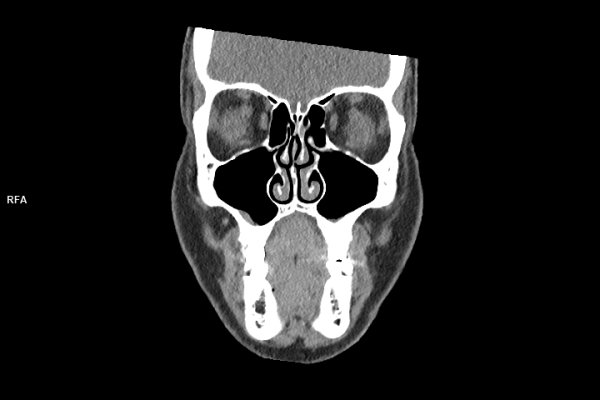

CT Untersuchung Bild

Detailbild MRT